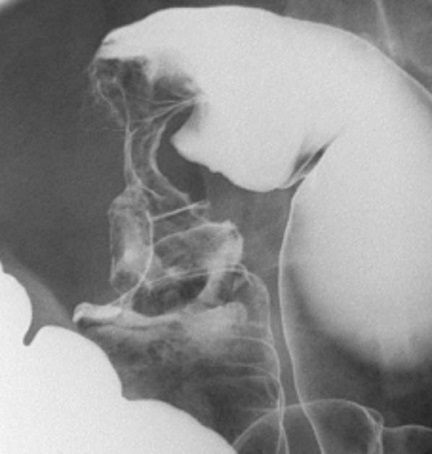

Image de lavement

baryte mono de contrast et double de contrast au

stade avance de cancer du colon est image stenosant en

circonferentiel du colon sigmoide et image laculaire

en bourgeon irregulier s'il situe au coecum

Aspect radiuologique stenosant en trognon

de pomme d'une adenome carcinoma du colon gauche

sigmoidienne .C'est image stenosant symetrique

d'une portion du colon a bord tres irregulier .

Image radiologique de lavement baryte mono de contrast |